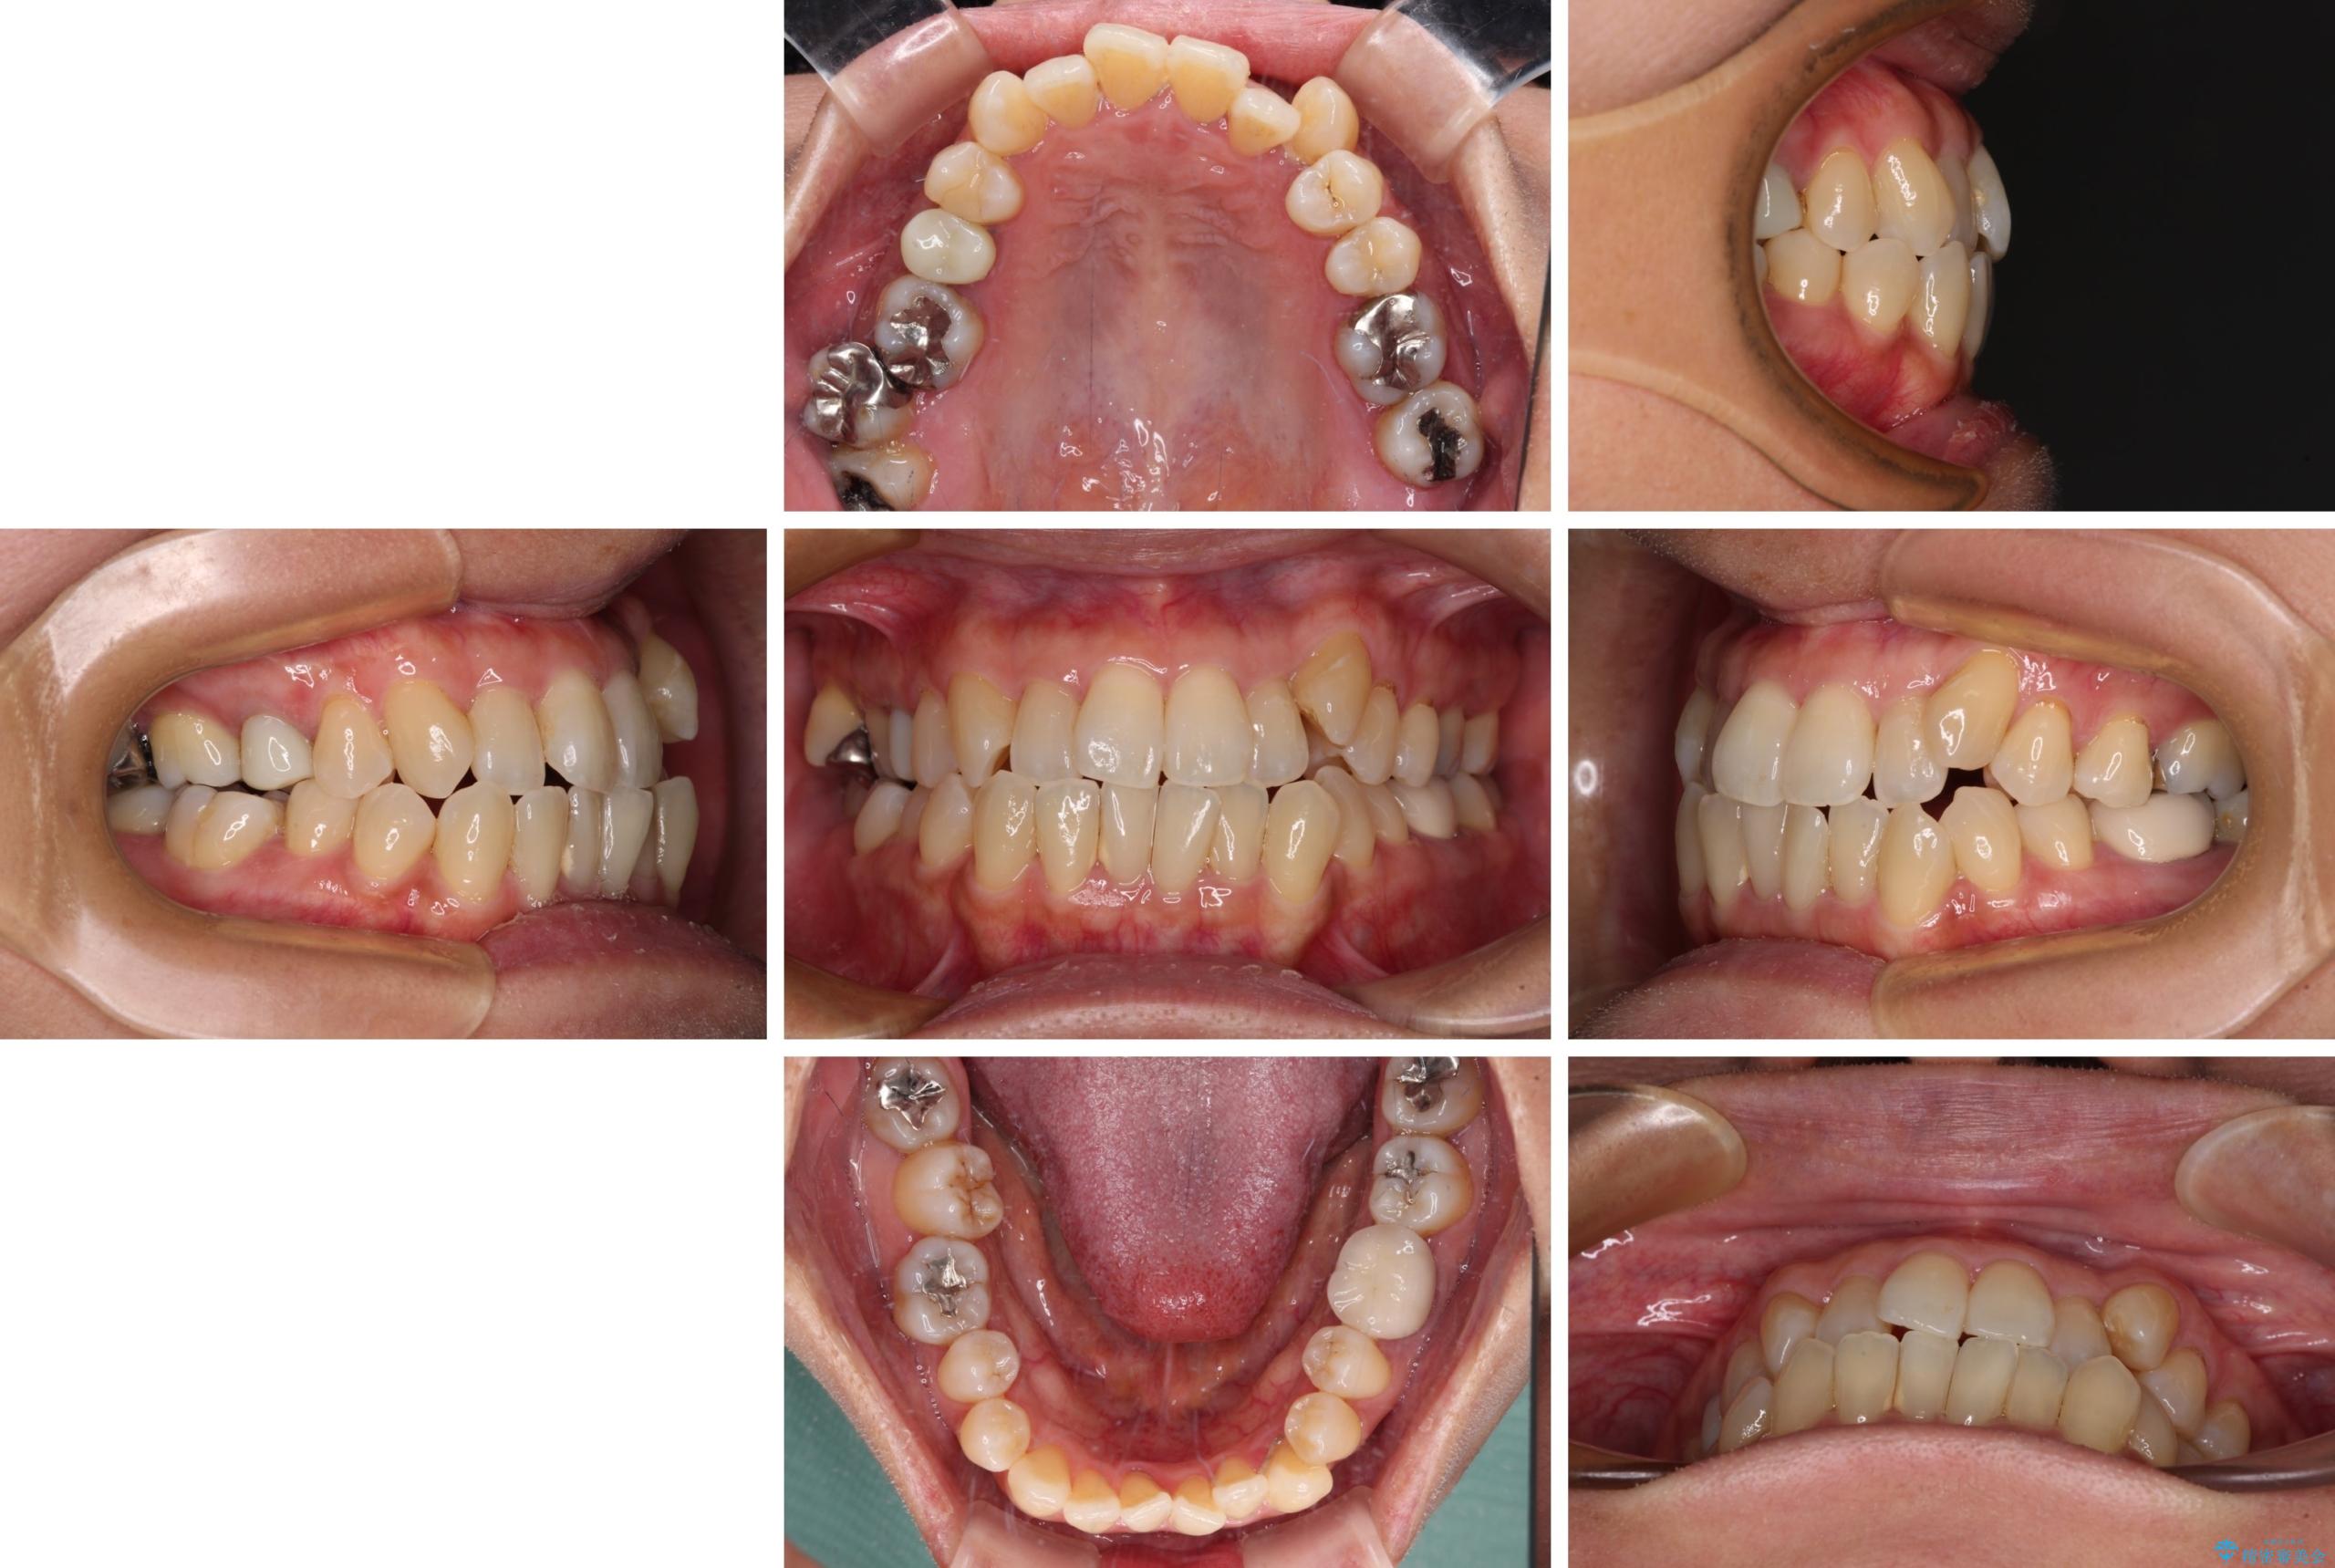

- 前歯のデコボコや八重歯を治したいとのことで来院された患者様です。

受け口傾向の骨格であり、前歯はクロスバイトまたは切端咬合となっており、下顎を中心に歯列全体の後方移動を行い、IPR(歯と歯の間を削る)によってデコボコが解消するように設計し、インビザラインにより治療を行うこととしました。

受け口傾向のインビザライン矯正は比較的治療を行いやすいため、きれいに仕上げることができました。舌の突出癖が顕著であったため、改善のためのトレーニングをしっかりと行っていただきました。